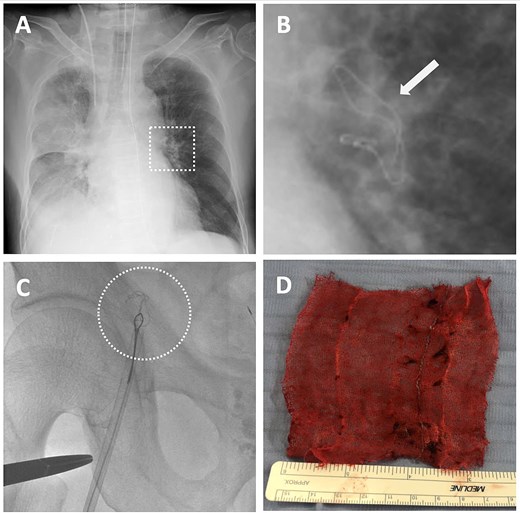

Detection of intravascular surgical gauze on radiograph and the retrieval process from the left pulmonary artery (LPA) using an endovascular technique with the right femoral vein approach. (A) X-ray image of the lung immediately after the operation. (B) The enlarged X-ray image shows the contrast of the surgical gauze at the hilum of the left lung (indicated by the arrow). (C) The snare catheter captured the surgical gauze in the LPA, passed through the right ventricle and atrium, and proceeded to the inferior vena cava and the right external iliac vein. (D) The surgical gauze was successfully retrieved through the right femoral vein.

On postoperative day (POD) 1, the patient developed hypoxemia (SpO₂ = 78%). A chest X-ray revealed a linear radiopaque shadow in the left hilar region (Fig. 3A and B). A CT confirmed the missing gauze had migrated intravascularly and was lodged in the LPA. A retrospective review of the intraoperative chest X-ray showed that the gauze had already reached that location but was missed.

Endovascular retrieval was performed 27 hours postoperatively under general anesthesia. A 12F sheath was placed via the right femoral vein. A 5F, 100-cm Headhunter catheter was advanced into the LPA guided by a 0.035-in, 260-cm Radifocus wire and then exchanged for an 8F, 90-cm guiding catheter (FUBUKI, Asahi Intecc). A 6F, 15-mm Amplatz gooseneck snare was introduced and navigated past the gauze into the distal LPA. The gauze was successfully grasped and pulled back through the LPA, cardiac chambers, IVC, and right iliac vein (Fig. 3C). Surgical exposure and venotomy of the femoral vein were performed and the gauze was removed en bloc due to difficulty passing through the 12F sheath. The procedure lasted 136 minutes. A CT showed partial thrombus in the LPA branches the following day, which resolved within 7 days. No anticoagulation was required. The patient recovered without further complications and was discharged on POD 18.